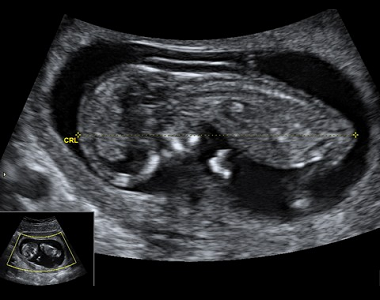

Screening v 1.trimestru

Ahoj bolky :)Tak jsme teď v pondělí byli na 1. velkém UTZ bylo to něco úžasnýho a nezapomenutelnýho!!! Viděli jsme toho našeho andílka snad ze všech stran, pan doktor nám vše vysvětloval, slyšeli jsme...

Diskuze 3